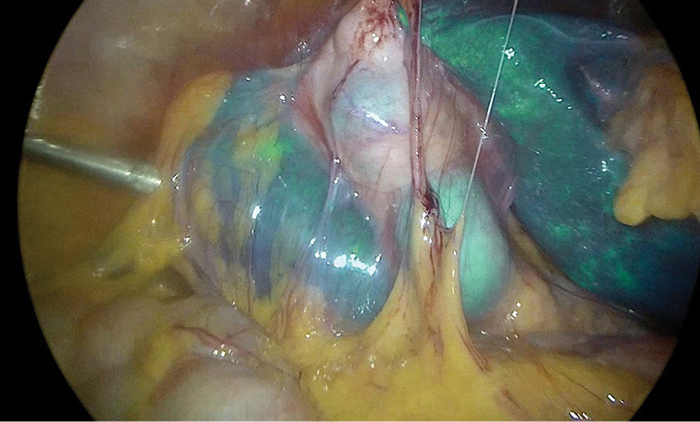

The treatment options for this patient were discussed at the multidisciplinary medical committee and the laparoscopic cholecystectomy with indocyanine green (ICG) fluoroscopy was chosen (Figure 2). Four trocars were placed in the abdominal cavity. During the surgery, the cystic duct was noticed, dissected separately from the cystic artery, and both separately clipped. The gallbladder was dissected, the subhepatic space was washed and the drain was left. The aponeurosis was sutured with three stitches of Monofilament. The post-operative period was uneventful, and the patient was discharged from the hospital.

Figure 2. Laparoscopic cholecystectomy with indocyanine green (ICG) fluoroscopy